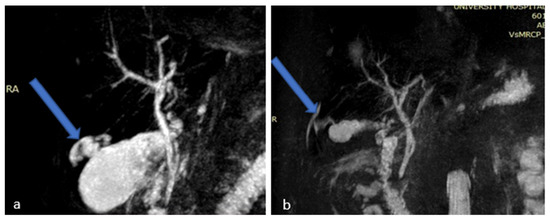

2.2. Case 2